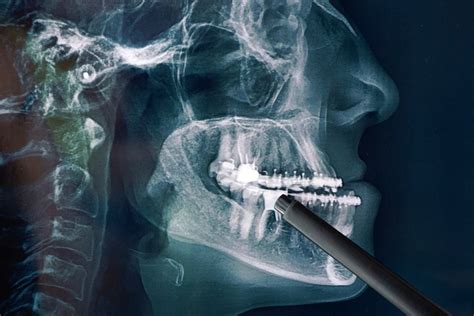

Radiología Maxilofacial y Oral

Los radiólogos orales y maxilofaciales son los que se encarga de realizar e interpretar las imágenes orales y de los elementos adyacentes. A través de estas se identifican diferentes enfermedades y afecciones en la boca y la estructura maxilofacial. Cuando se habla de imágenes orales y maxilofaciales se incluyen, las radiografías, resonancias magnéticas, imágenes intraorales, ultrasonidos y otras. Las radiografías ayudan a cualquier especialista. Ya que a través de estas es posible ver el desarrollo de los dientes, encontrar caries, observar las raíces de los dientes y la estructura ósea.